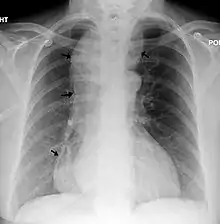

| Chest x-ray of an individual with achalasia. The arrows point to the areas of extreme esophageal dilation. | |

Achalasia, or oesophageal achalasia, is a disorder occurring in the lower oesophageal sphincter (LES). The LES fails to relax completely, resulting in frequent vomiting and regurgitation, usually one to two hours after meals.[4][3] If untreated, the long-term health of the individual will be compromised, leading to the development of dysphagia, weight loss and chronic aspiration.[4] It is very rare in children, especially siblings.[3] Mortality, specifically in young children, can occur.[3]

A positive barium swallow will display the narrowing of the distal oesophagus in a 'bird beak' or 'champagne class' fashion, aperistalsis, minimal LES opening and oesophageal dilation as the main indicator of the disease.[4][5] Minimal barium will be present in the stomach.[5] However, these diagnostic findings are not always present in the early onset of the disease and so a normal oesophagogram is not an indication of a lack of disease.[5]